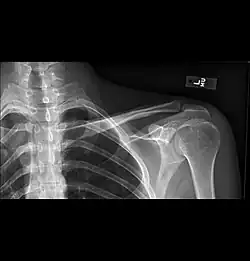

- Clavicular companion shadow is a thin soft-tissue stripe along the upper edge of the clavicle.[1]